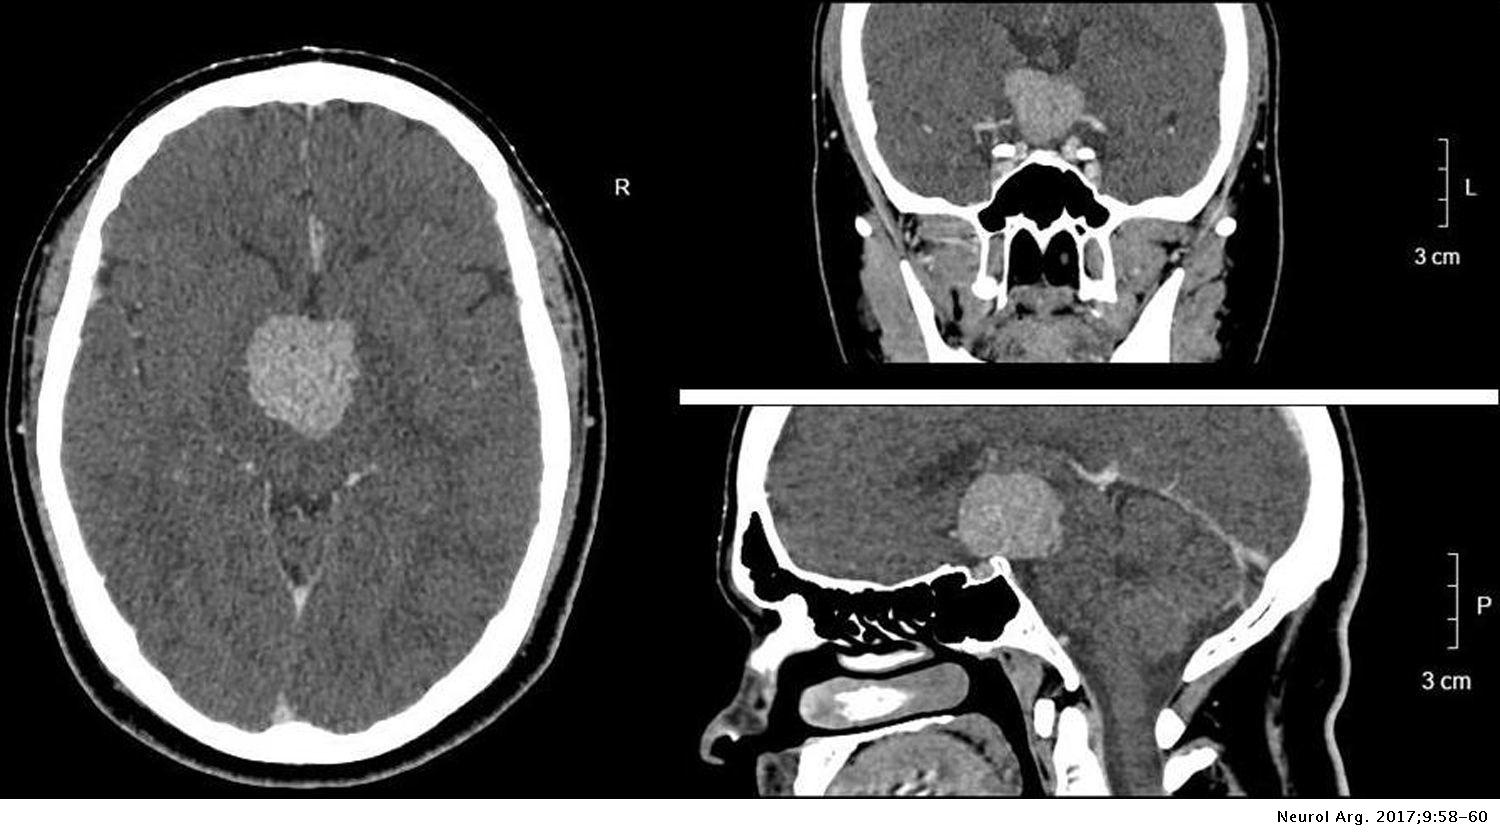

Pituicitoma hipofisario Neurología Argentina

Disección arterial vertebral bilateral como manifestación inicial del síndrome de Cushing